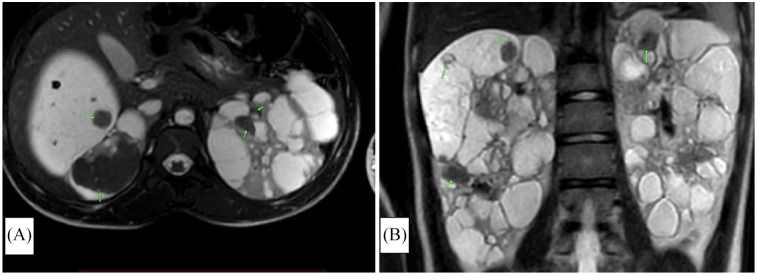

结节性硬化症(TSC)是一种罕见的多系统神经皮肤综合征,具有广泛的临床表现。我们提出一个14岁的青少年女性谁提出了历史的面部血管纤维瘤,因为年龄8个月。查体时发现面部多发血管纤维瘤及其他多发性皮肤表现。头部和腹部MRI显示皮质结节,多发双侧脑室周围和室管膜下结节病变,钙化,双侧肾脏肿大伴多发大小不等的双侧肾脏血管平滑肌脂肪瘤,双侧多囊肾背景,胸部MRI未见明显变化。诊断TSC采用临床诊断标准,其中包括主要和次要特征。由于缺乏资源,无法通过基因研究进行诊断。管理是多学科的,需要每6个月定期监测一次,以监测疾病进展并在出现并发症时进行管理。该病例说明了在资源匮乏的环境中,如赞比亚,需要多学科方法来解决TSC的各种临床表现,以及TSC的诊断挑战、治疗限制和心理影响,因为那里获得先进治疗的机会有限。

Tuberous sclerosis complex (TSC) is a rare multisystemic neurocutaneous syndrome with a wide spectrum of clinical manifestations. We present a case of a 14-year-old adolescent female who presented with a history of facial angiofibromas since the age of 8 months. Physical examination was remarkable for multiple angiofibromas on the face, and other multiple cutaneous manifestations of TSC. MRI of the head, and abdomen revealed cortical tubers, multiple bilateral periventricular and subependymal nodular lesions, calcifications, and bilateral kidney enlargement with multiple bilateral renal angiomyolipomas of varying sizes in a background of bilateral polycystic kidneys, MRI of the chest was unremarkable. A diagnosis of TSC was made using the clinical diagnostic criteria which consist of major and minor features. A diagnosis using genetic studies could not be made due to a lack of resources. Management was multidisciplinary and regular monitoring every 6 months will be required to monitor disease progression and manage complications as they arise. This case illustrates the multidisciplinary approach needed to address the diverse clinical manifestations of TSC and the diagnostic challenges, treatment limitations, and psychological impact of TSC in low-resource settings like Zambia where access to advanced therapies is limited.